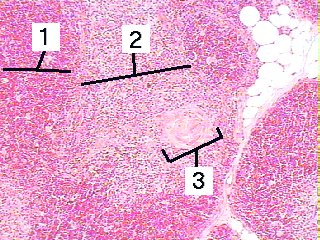

A higher magnification of the thymus showing the Hassall bodies.

Fig 062-002 1. Cortex

2. Medulla

3. Hassall body